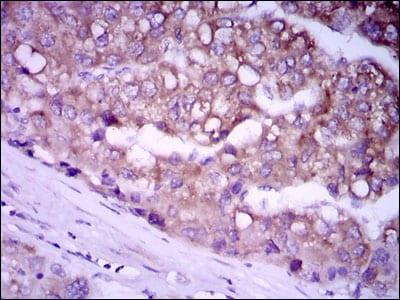

细胞水平的验证更具生理意义。选取高表达GPC3的肿瘤细胞株、低表达或不表达GPC3的正常细胞株及其他肿瘤细胞株,通过免疫荧光、流式细胞术等方法,观察抗体在细胞表面的结合情况。仅在高表达GPC3的细胞株中出现特异性结合信号,才能初步确认抗体在细胞层面的特异性。此外,免疫沉淀实验可进一步验证抗体与内源性GPC3的结合能力,排除非特异性结合带来的假阳性结果。

交叉反应是影响抗体特异性的重要因素,尤其是与人体正常组织或其他蛋白的交叉结合,可能引发不良反应,因此必须进行系统检测。采用人类组织芯片,对抗体与不同组织的结合情况进行筛查,重点关注肝脏、肾脏等GPC3可能低表达的正常组织,确保抗体仅与肿瘤组织中的GPC3结合,不与正常组织发生交叉反应。